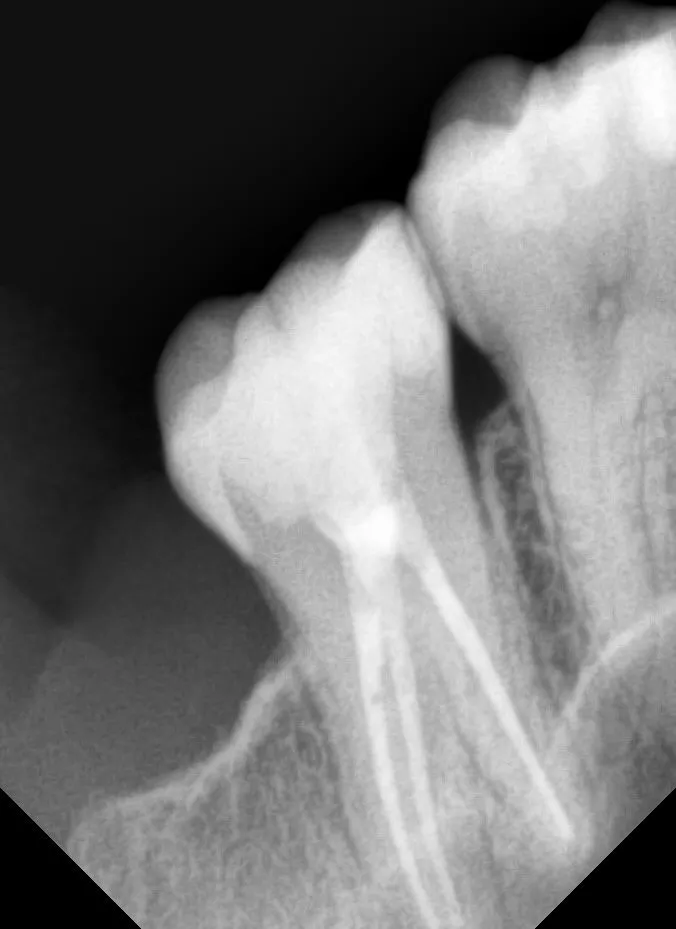

Пациентка была направлена коллегой стоматологом терапевтом для эндодонтического лечения и восстановления зуба 1.7 по диагнозу острый пульпит. Коллега произвел снятие острой боли и постановку временной пломбы. Основная проблема, которой сообщила нам и пациентка и врач стоматолог затрудненное открывание рта и повышенный рвотный рефлекс.

Произвели эндодонтическое лечение зуба 1.7 и восстановление зуба постоянной пломбой.